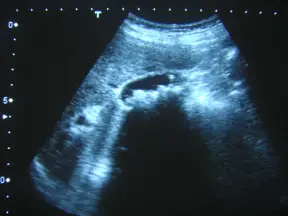

下圖為右上腹部超音波掃描圖,最可能的診斷為:

超音波影像顯示在右上腹膽囊腔內,有多個高迴聲小結節,並在其後方呈現典型、乾淨的三角形posterior acoustic shadowing;膽囊壁邊界清楚,未見增厚或因氣體存在而失真;高迴聲點排列依重力方向集中於膽囊底部,未見散在ring-down或dirty shadow現象。

- 選項A 產氣性膽囊炎:超音波應見因氣體所致的reverberation artifact(ring-down artifact)或dirty shadowing,而非乾淨聲影;常伴膽囊壁增厚及周圍組織發炎改變,本影像無此所見,故不符(pubmed.ncbi.nlm.nih.gov)。

- 選項B 產氣性肝膿瘍:病灶位於肝實質,超音波呈現液化區伴不規則氣體回聲(dirty shadowing),位置與本例配景不符。